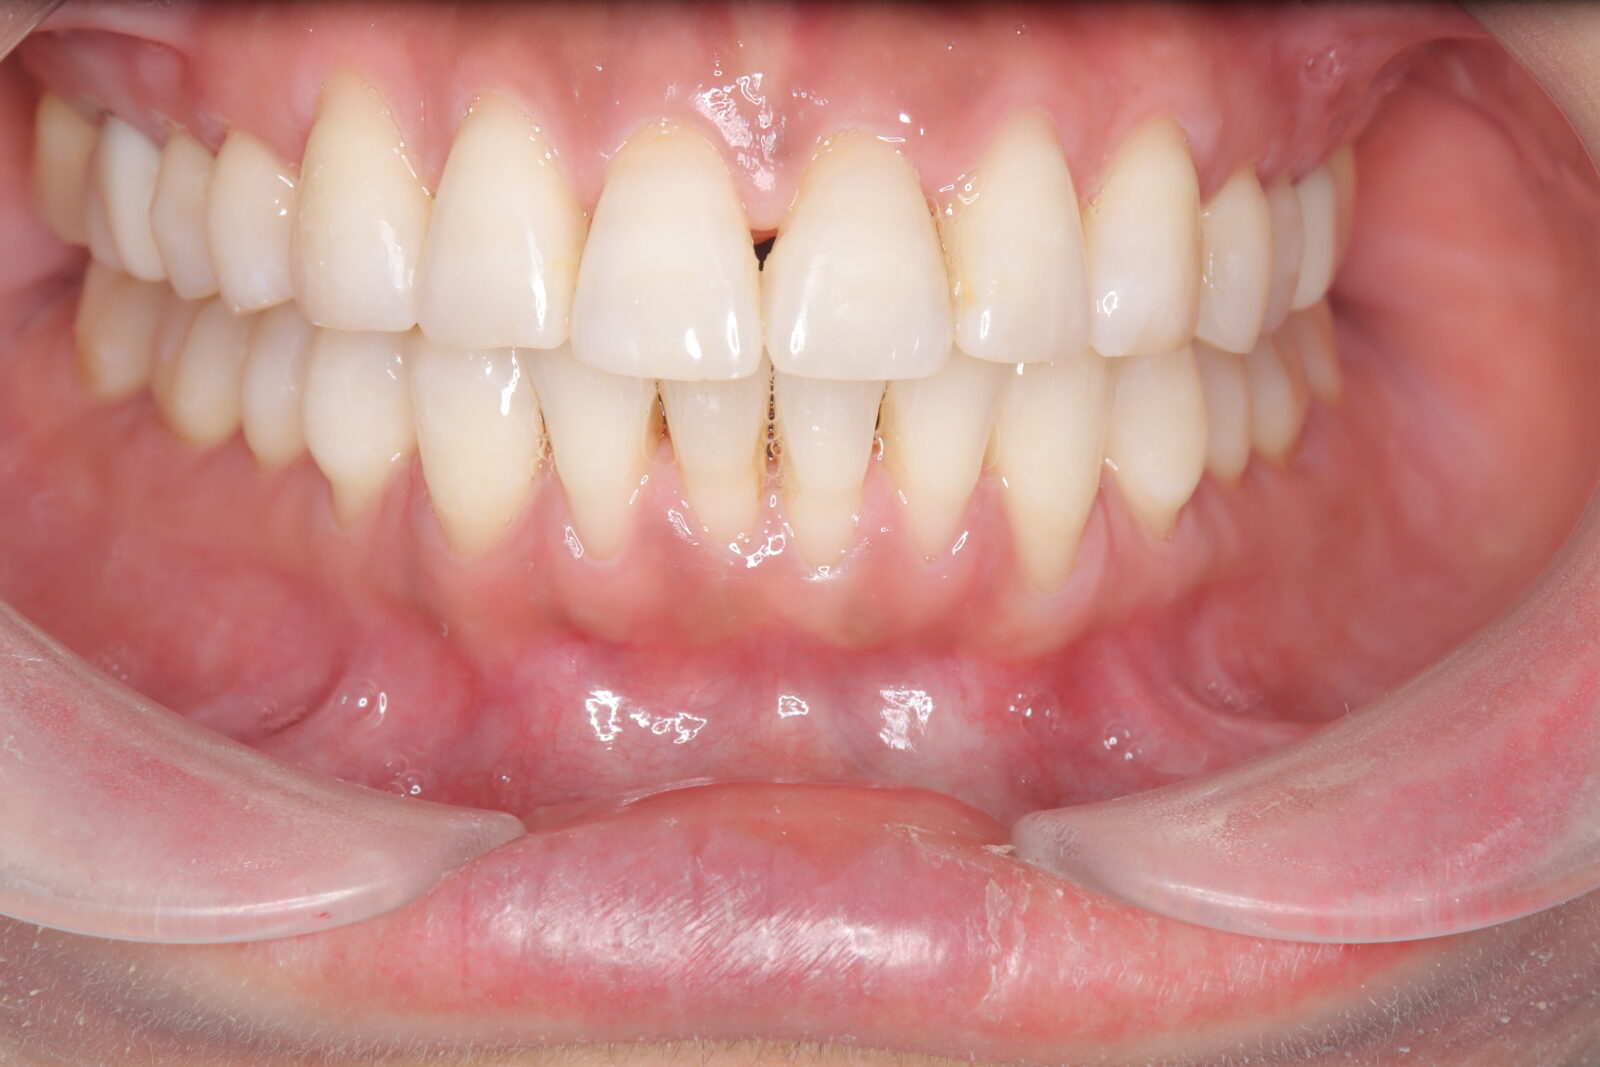

インビザライン(全体矯正)+ホワイトニングコースの症例

歯の裏に歯が隠れてしまっていたため、全体矯正(非抜歯+遠心移動)で美しく改善。

・費用:935,000円(税込)

・治療期間:30ヶ月

・通院回数:30回

・35歳女性

-リスクと副作用-

・長時間マウスピースを装着するため、むし歯や歯周病のリスクがある。治療後はリテーナーを装着しないと後戻りしてしまうリスクがある。

・ホワイトニング剤の影響で知覚過敏が起こる可能性がある。色が徐々に戻る可能性がる。